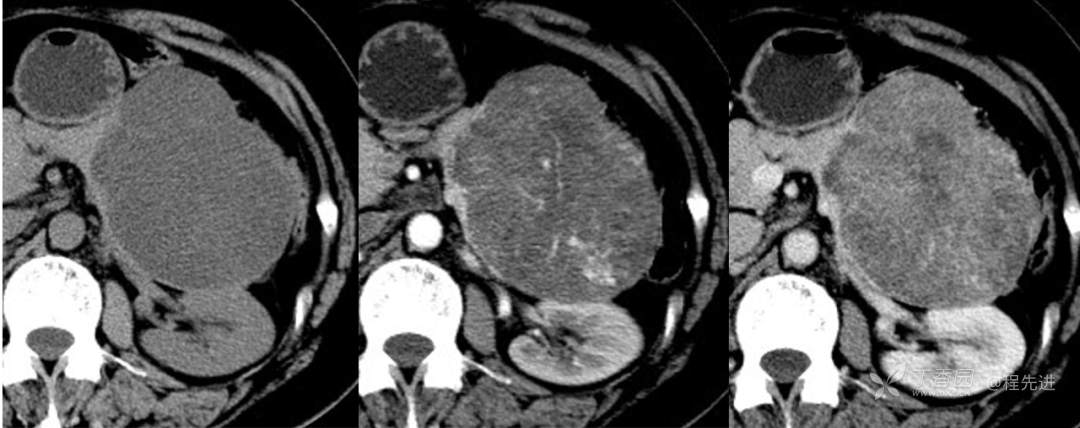

CT平扫

CT增强动脉期

CT增强门静脉期

CT值

平扫约22HU,动脉期约44HU,门脉期约70HU